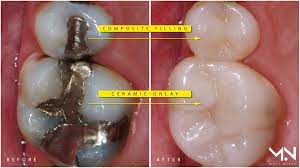

If the filling has come out because of more extensive damage to the bone or root your dentist will discuss a plan for further treatment which could include a crown or root canal. If a simple replacement filling is all thats needed your dentist will discuss your options including the familiar silver-colored amalgam the increasingly popular composite resin gold and porcelain inlay. 5 weeks pregnant and mercury filling fell out.

This can widen the cavity and reduce the strength of the bond holding the filling in. When a composite or an amalgam have decay underneath it can be very difficult to simply replace the filling. Amalgam filling measured 25 microamperes.